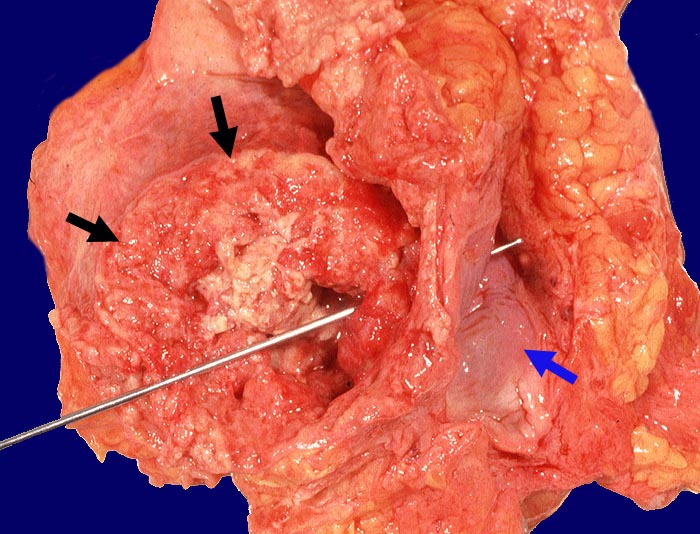

Harnblasenkarzinom mit vesikovaginaler Fistelbildung

Polypöser Tumor der Harnblase. Die Sonde steckt in der tumorbedingten vesikovaginalen Fistel. Rechts ist die graue glatte Vaginalschleimhaut erkennbar.

Wenig differenziertes Urothelkarzinom. Tumordurchmesser 10cm. Infiltration des perivesikalen Fettgewebes mit vesikovaginaler Fistelbildung.

St.n. mehrfacher transurethraler Blasenresektion